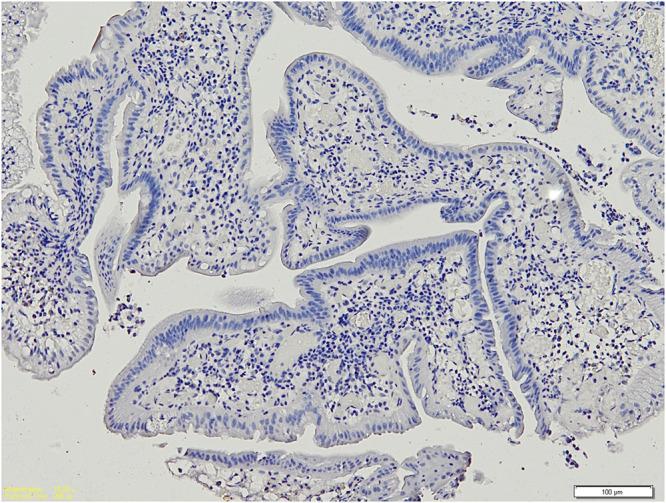

A retrospective observational study was carried out at a general hospital in West Java, Indonesia, from July 2019 to June 2024. Forty-four patients diagnosed with ampulla of Vater cancer were included. PD-L1 expression was evaluated using immunohistochemistry, and clinicopathological data were analyzed using chi-square, Mann-Whitney, and independent -tests.

There were 44 research subject. The PD-L1 expression was positive in 59.1% of patients and negatively associated with carcinoembryonic antigen (CEA) levels (p = 0.010). There was a significant association between PD-L1 positivity and lymph node involvement (p = 0.042) and clinical stage (p = 0.017). No significant association was found between PD-L1 expression and age, sex, histopathological grade, or distant metastasis.

PD-L1 expression in ampulla of Vater cancer is significantly associated with higher lymph node metastasis and advanced clinical stage but not with age, sex, or tumor differentiation. These findings suggest PD-L1 as a potential prognostic marker and therapeutic target.